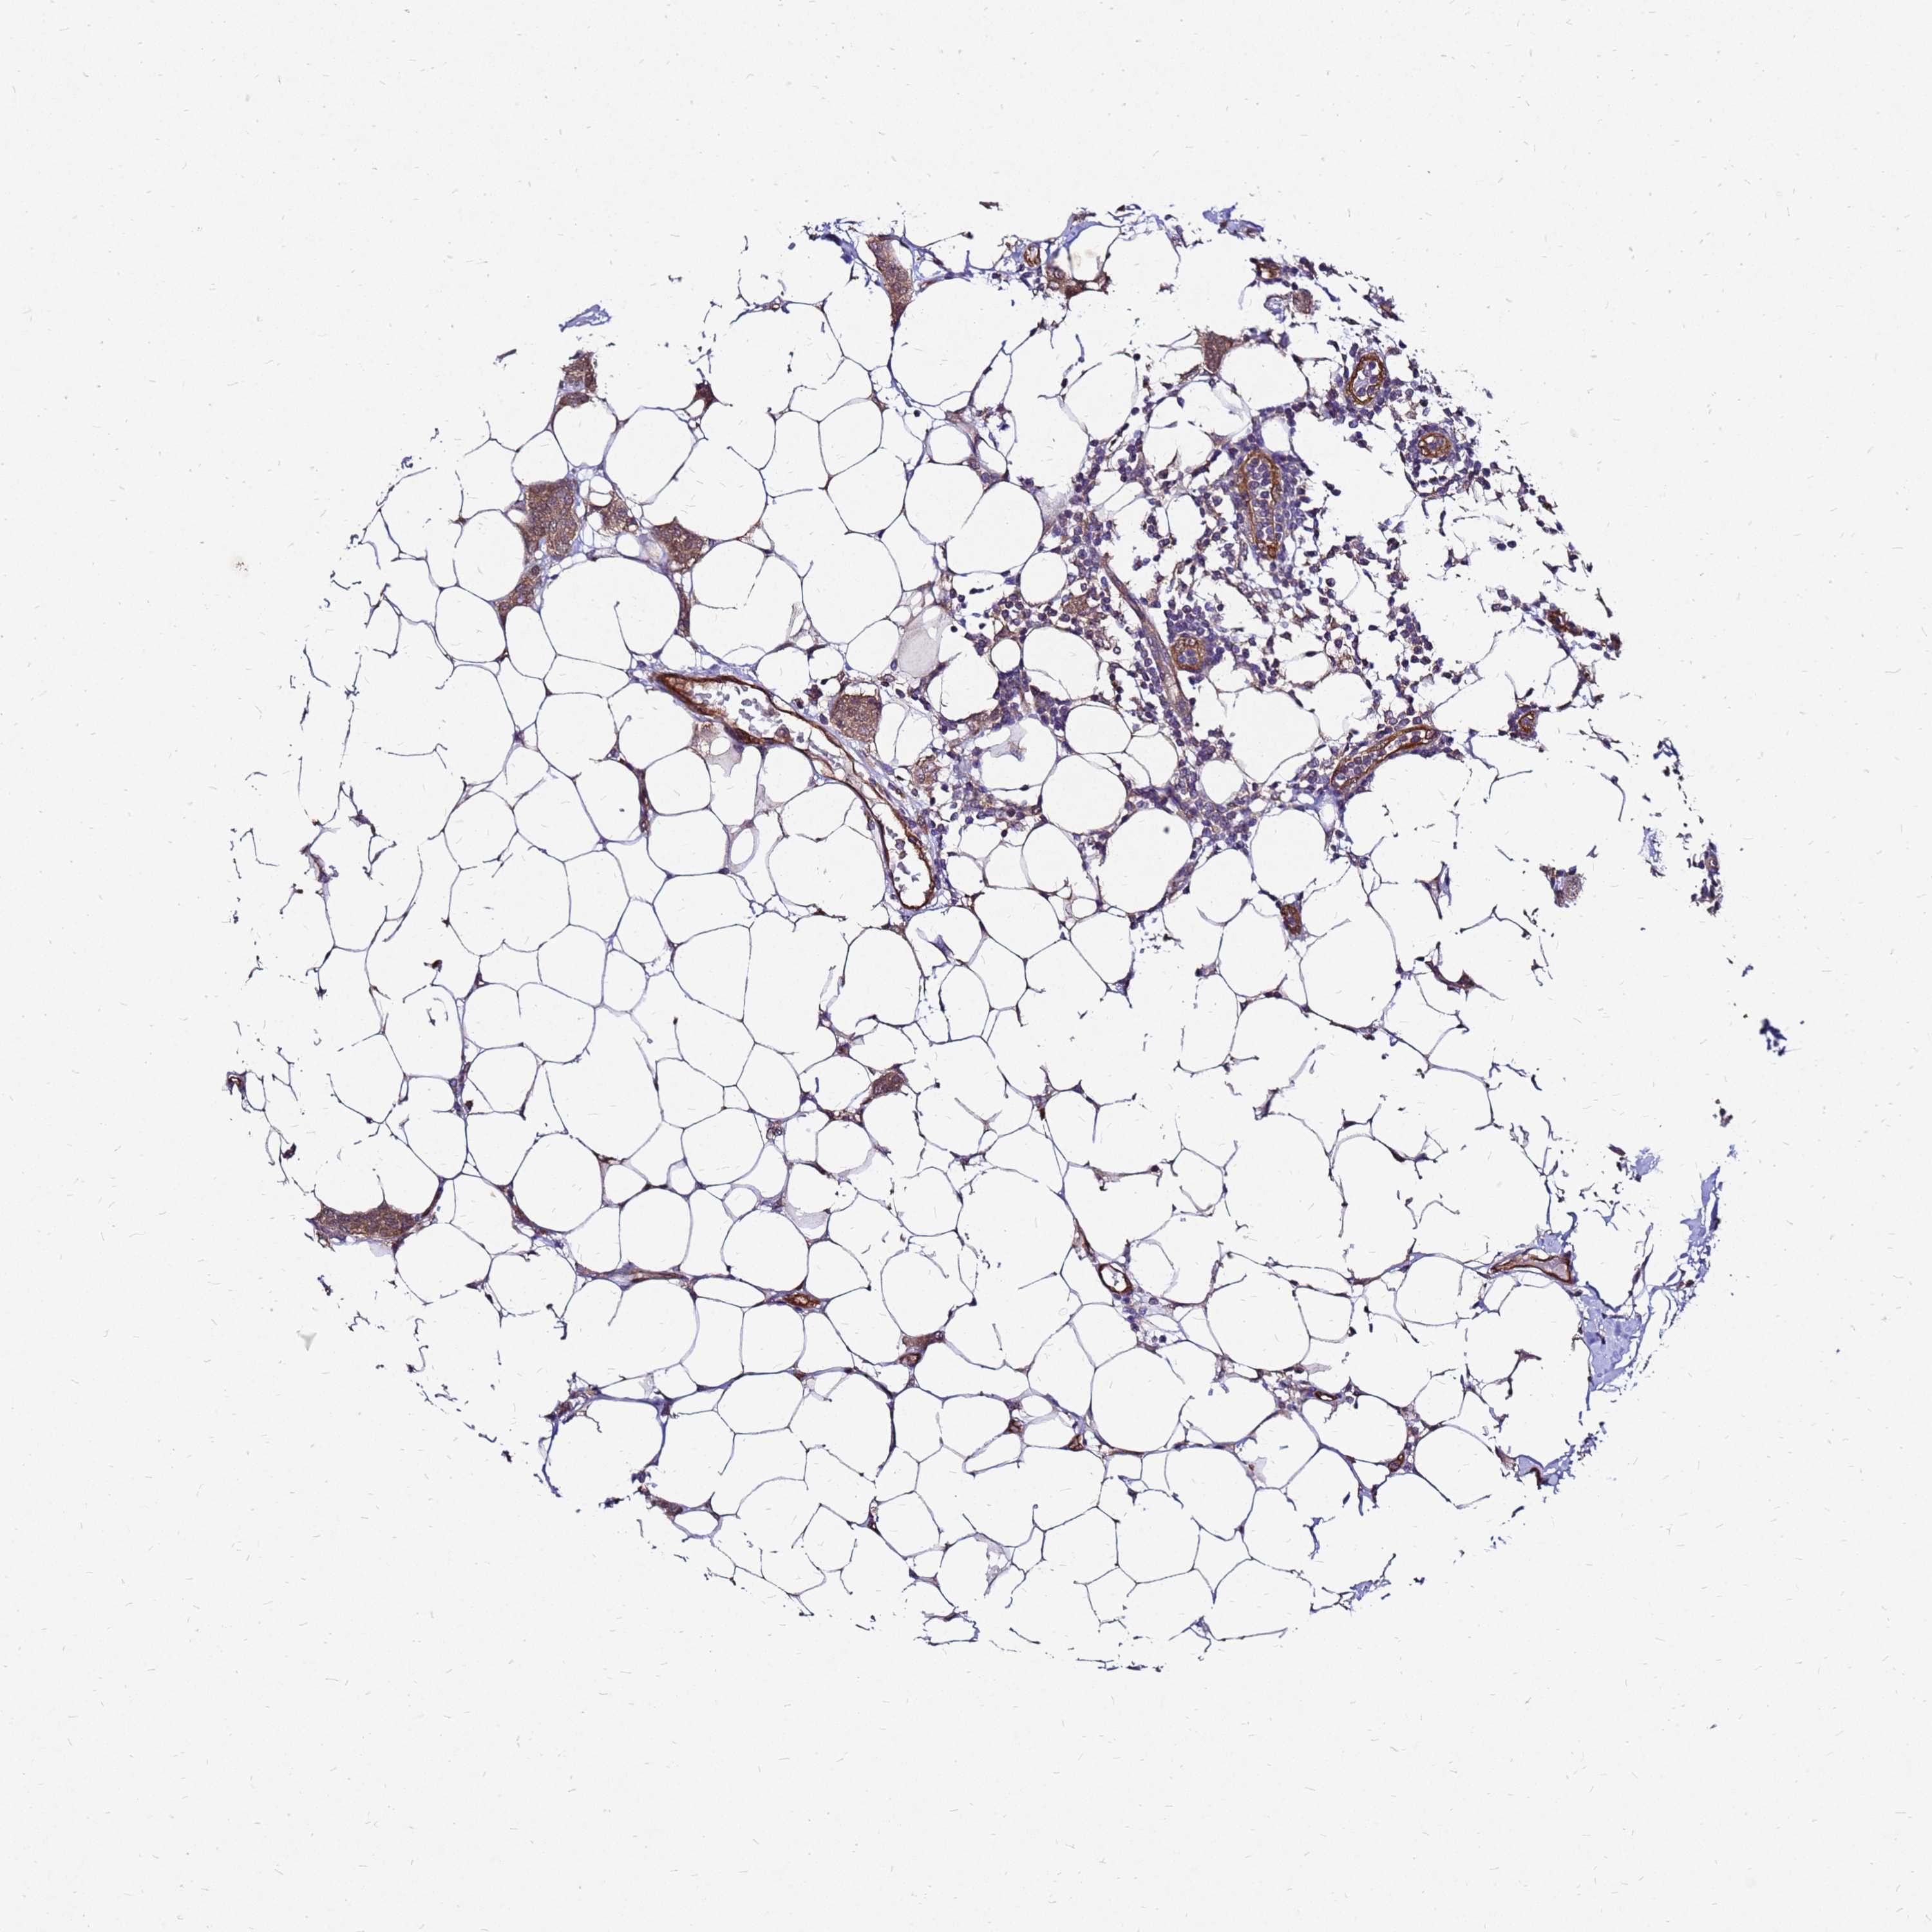

BRCA TCGA BRCA VALIDATION PROTEIN EXPRESSION

ANTIBODIES

AND

VALIDATION